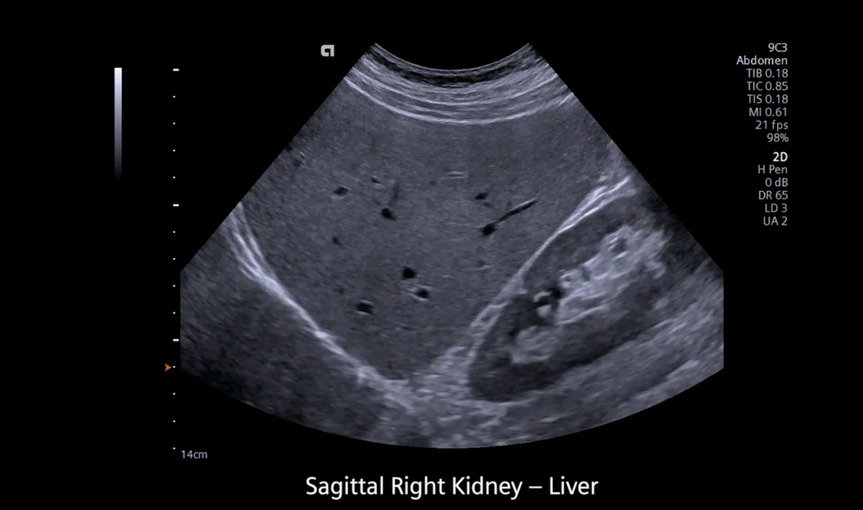

Кроме новой техники, можно заказать восстановленные медицинские системы: ультразвуковые сканеры, томографы, флюороскопы, ангиографы и хирургические установки С-дуга.